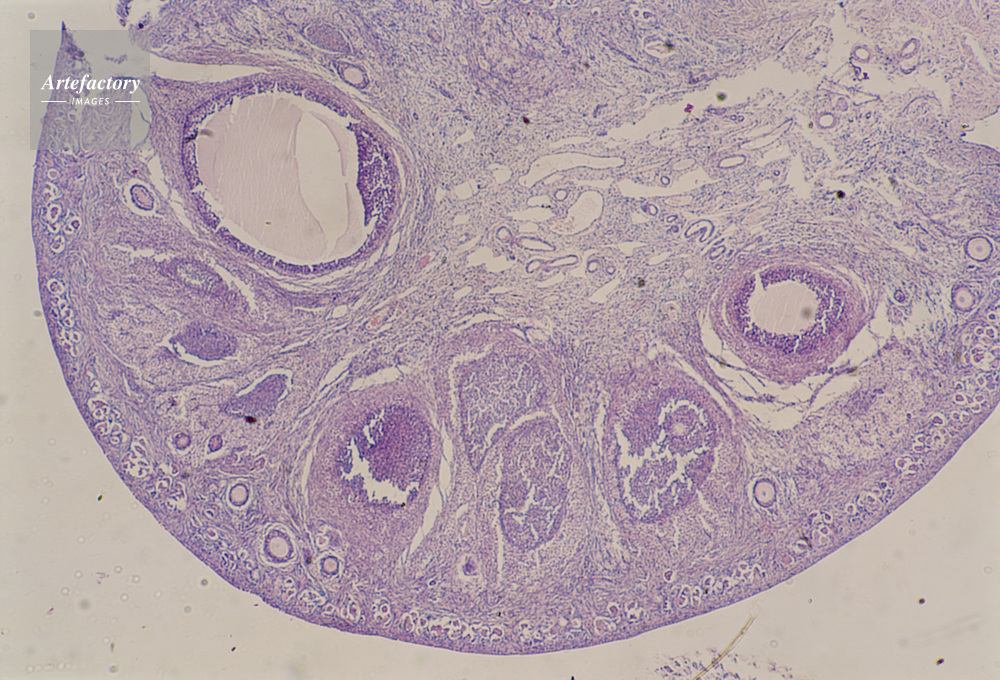

| 作品タイトル | 顕微鏡写真 | モデルリリース | なし | |

| キャプション | 卵巣,犬,20倍 | 制限事項 | ||

| ソース | ピクセル数 | 5552px × 3776px | ||